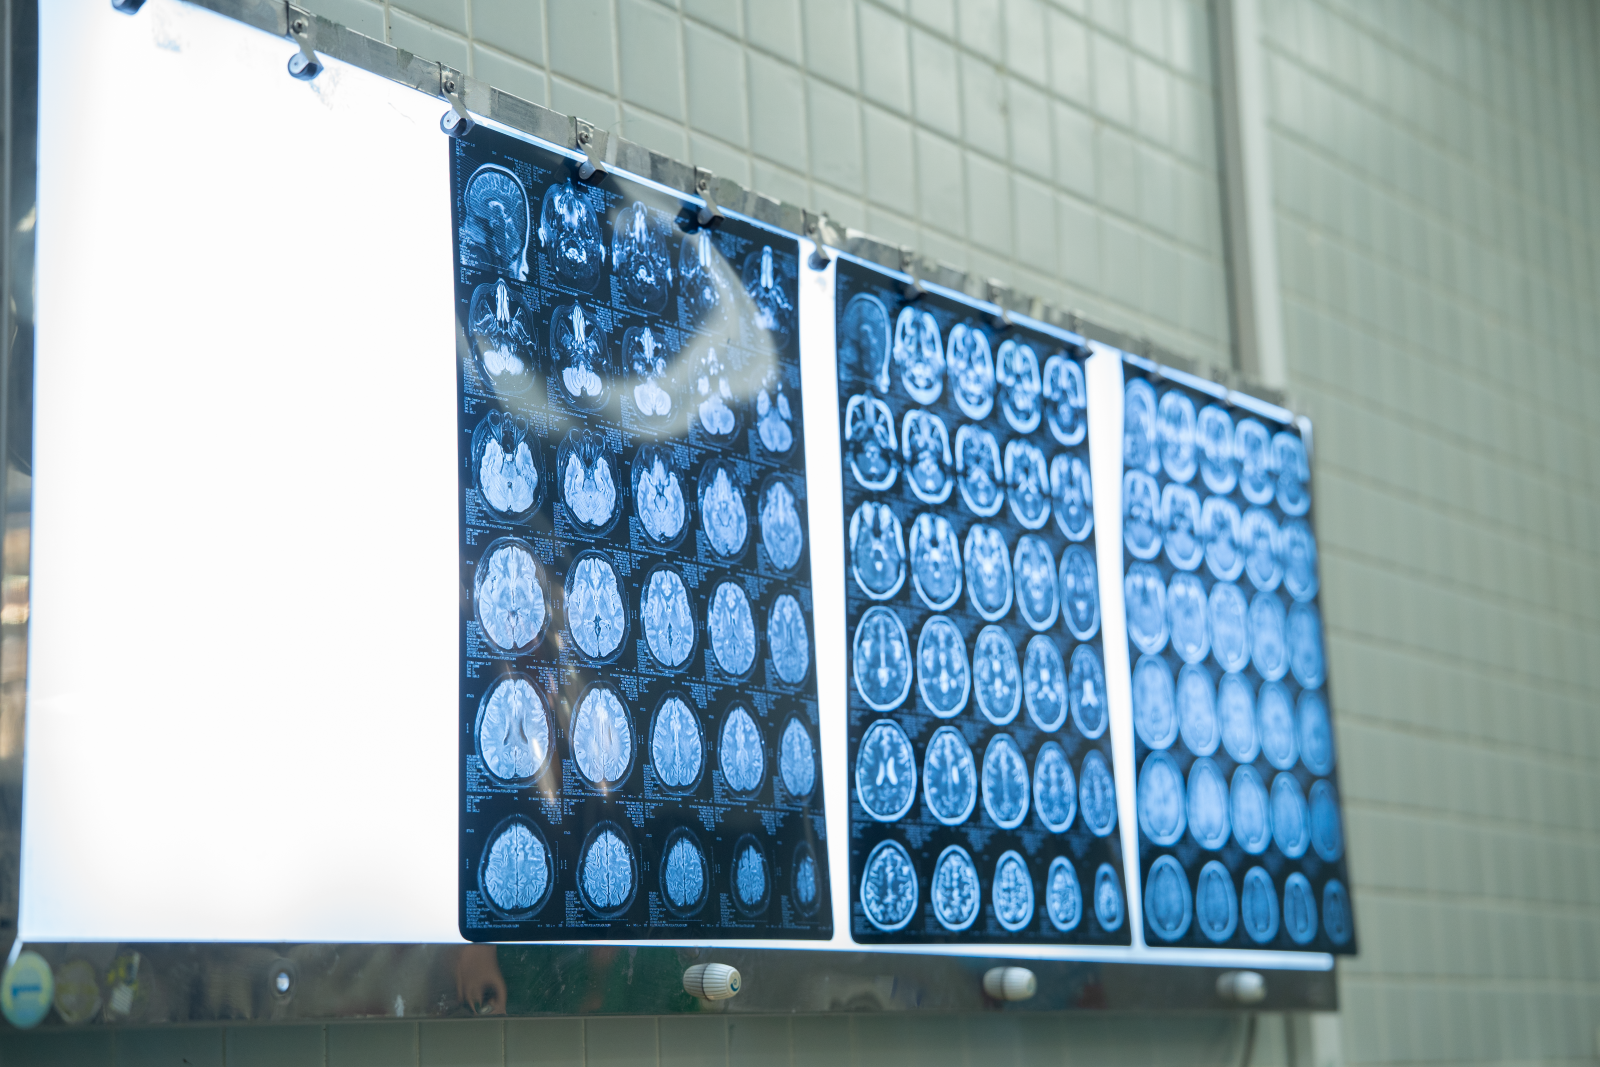

Kết quả chụp MRI tưới máu não và chụp mạch não số hóa xóa nền (DSA) ghi nhận hình ảnh điển hình của bệnh Moyamoya, một bệnh lý mạch máu não bẩm sinh.

Tại khoa Ngoại thần kinh Bệnh viện Chợ Rẫy, kết quả chụp MRI tưới máu não và chụp mạch não số hóa xóa nền (DSA) ghi nhận hình ảnh điển hình của bệnh Moyamoya, một bệnh lý mạch máu não bẩm sinh. Sau khi hội chẩn, ê-kíp điều trị quyết định thực hiện phẫu thuật bắc cầu động mạch não trong - ngoài sọ nhằm tái tạo lưu lượng tưới máu não cho vùng tổn thương.